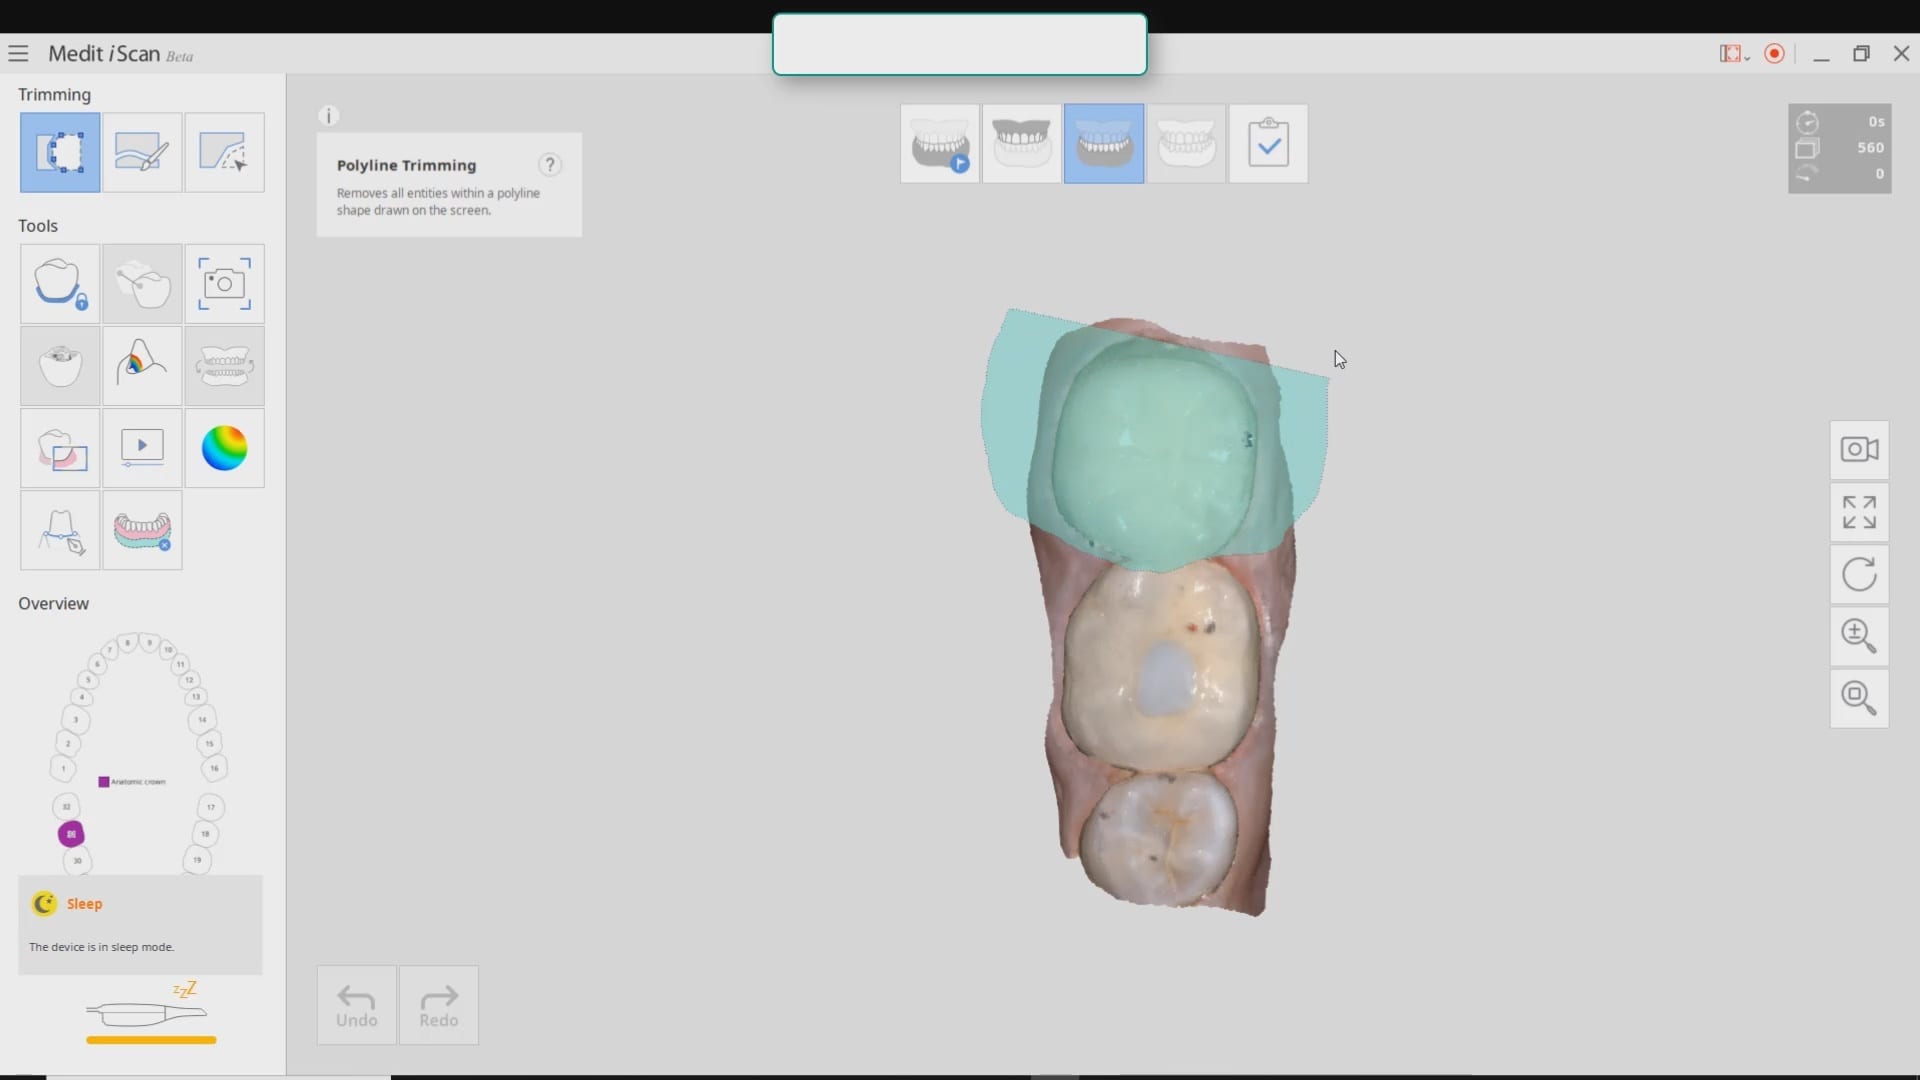

Second Molar Crown Replacement in Copy Mode

September 3, 2019In this case presentation, we feature a crown that needs to be replaced due to open margins and recurrent decay. With the Medit i500, after the patient is anesthetized and […]

In this case presentation, we feature a crown that needs to be replaced due to open margins and recurrent decay. With the Medit i500, after the patient is anesthetized and […]